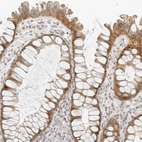

Immunohistochemical staining of human colon shows moderate cytoplasmic and membranous positivity in glandular cells.